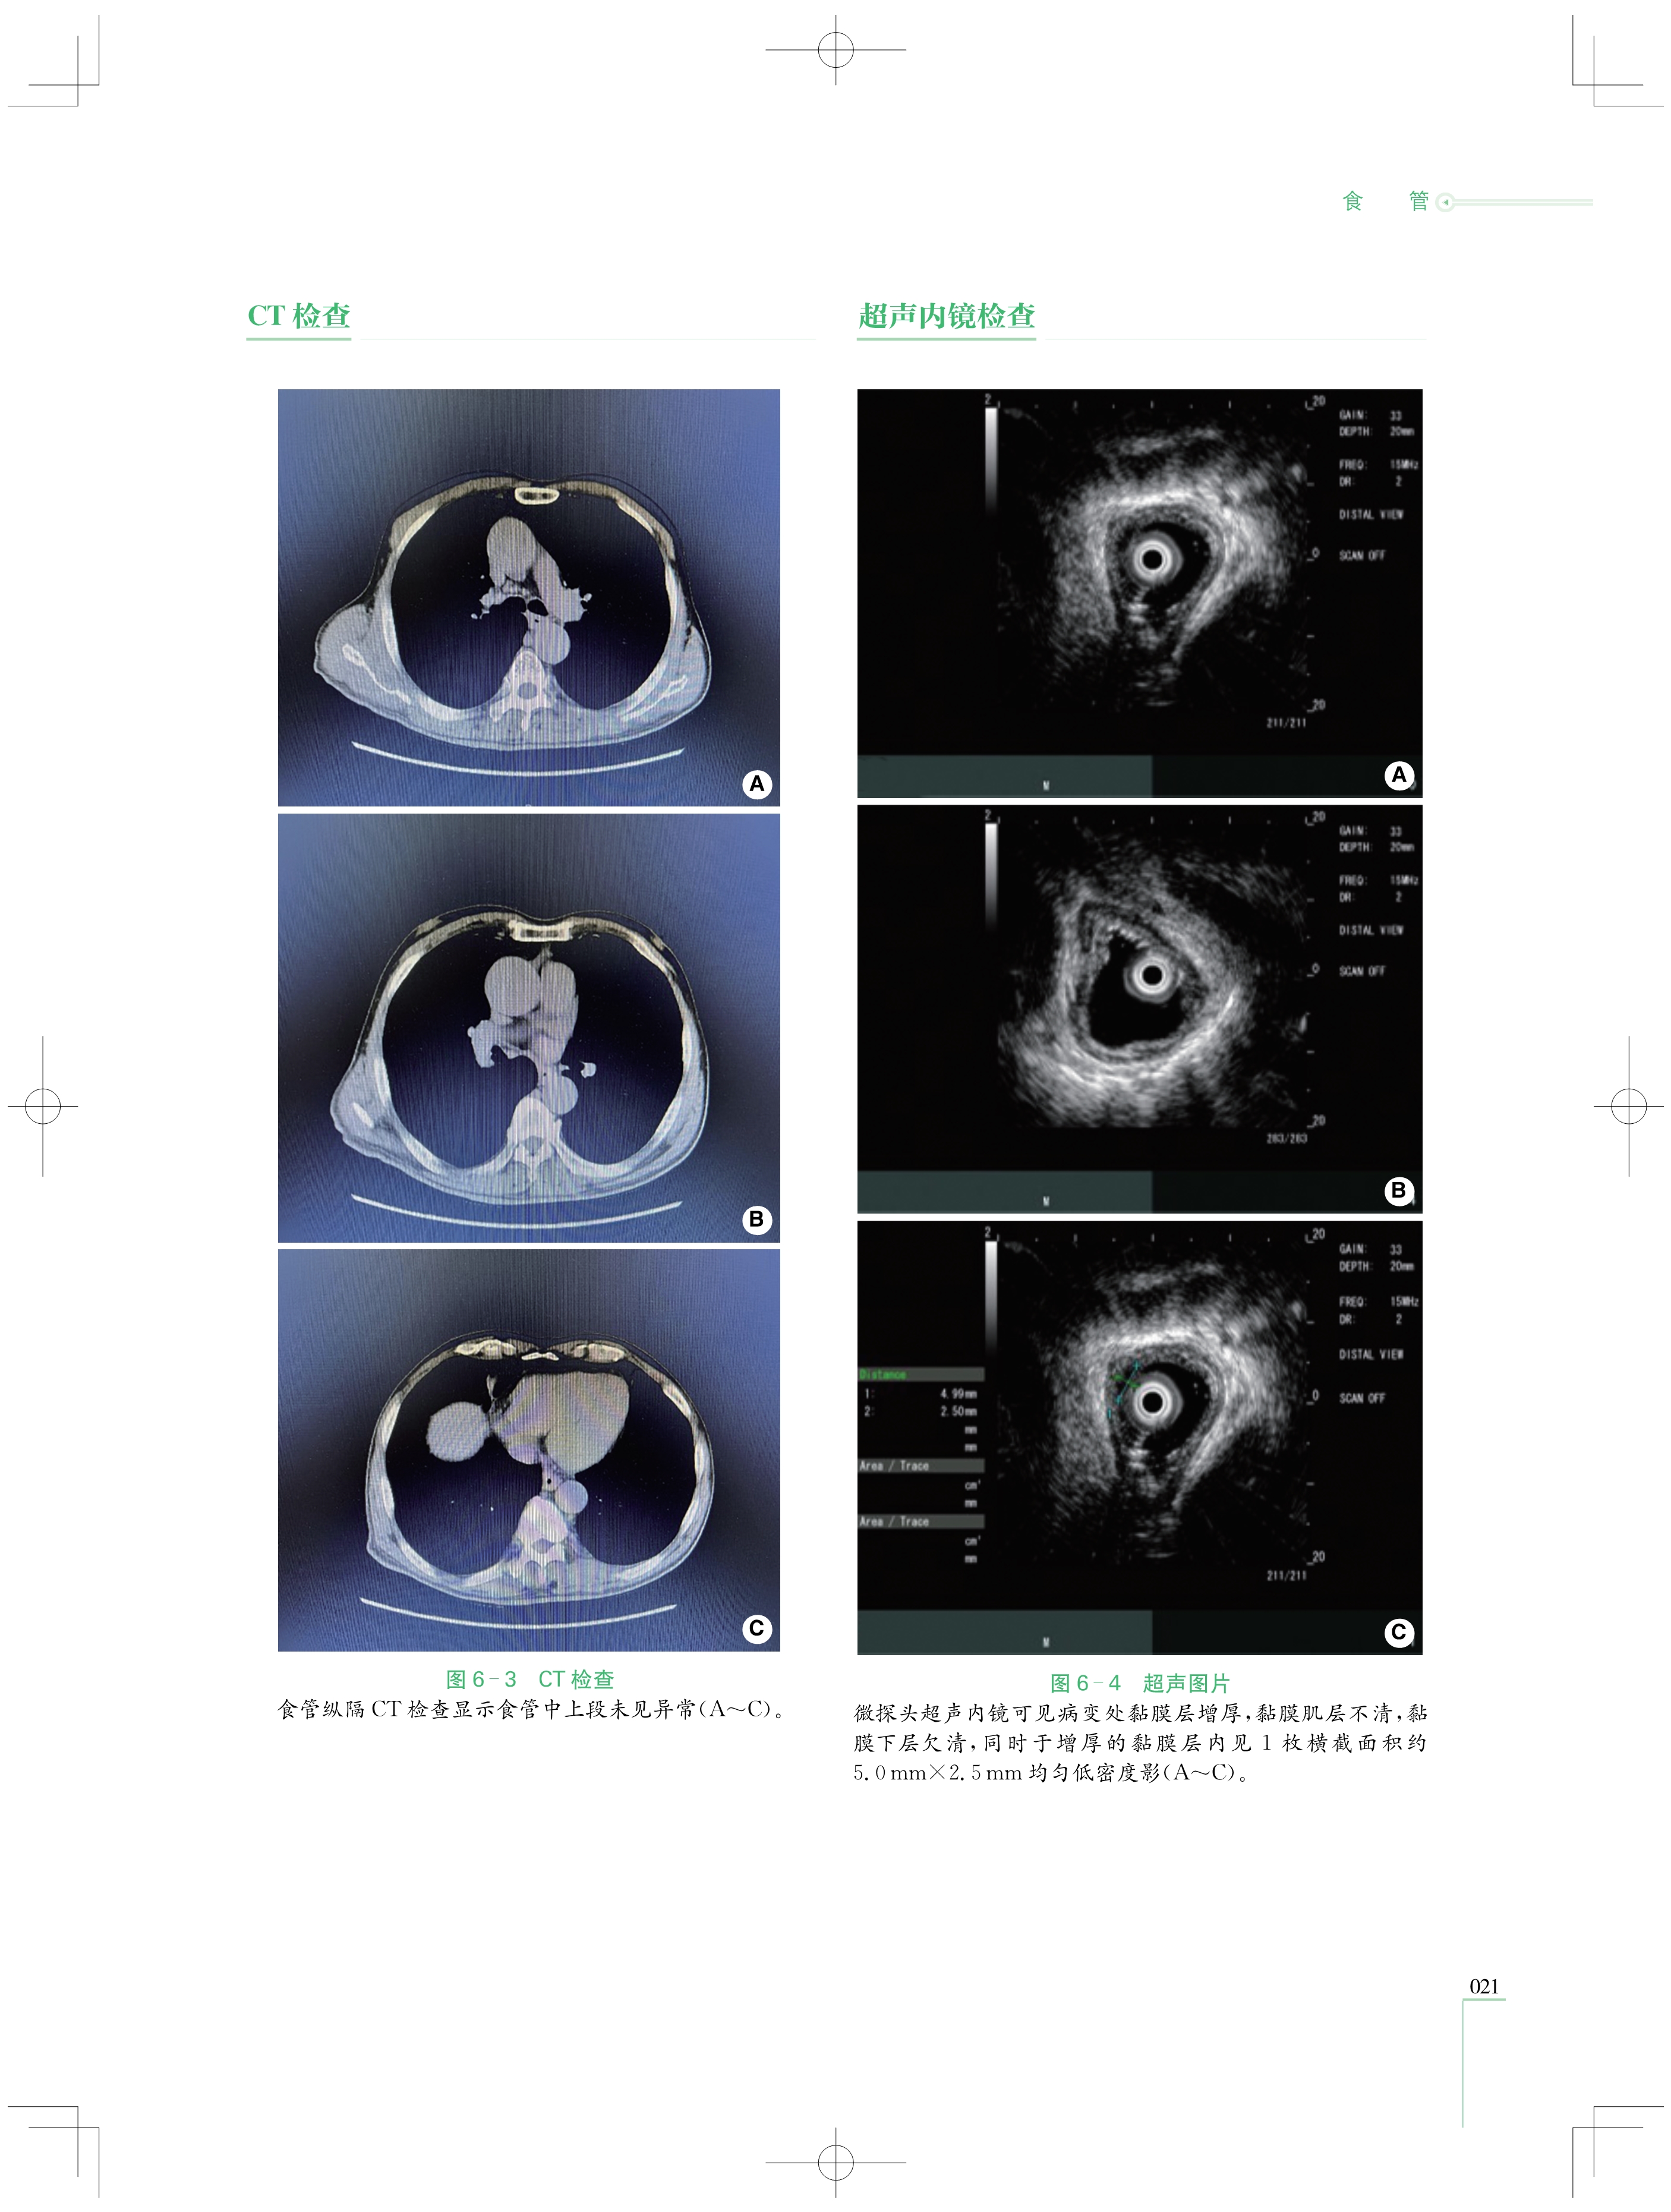

本书收集了第一届至第五届“ 中国介入性EUS视频大赛 ”的优秀获奖病例共计87例,涵盖超声微探 头及介入性超声内镜( EUS)两大领域,这些病例皆历经严格筛选,具有极高的代表性和典型性,全面覆盖了 消化系统的复杂疑难病症。从极为罕见的消化道黏膜下病变,到极易混淆的纵隔占位性疾病,每一个病例 都翔实还原了诊疗经过、超声图像与病理对照,为读者展现完整且严谨的诊断思维体系,帮助读者在复杂的 病情中抽丝剥茧,精准把握疾病本质。